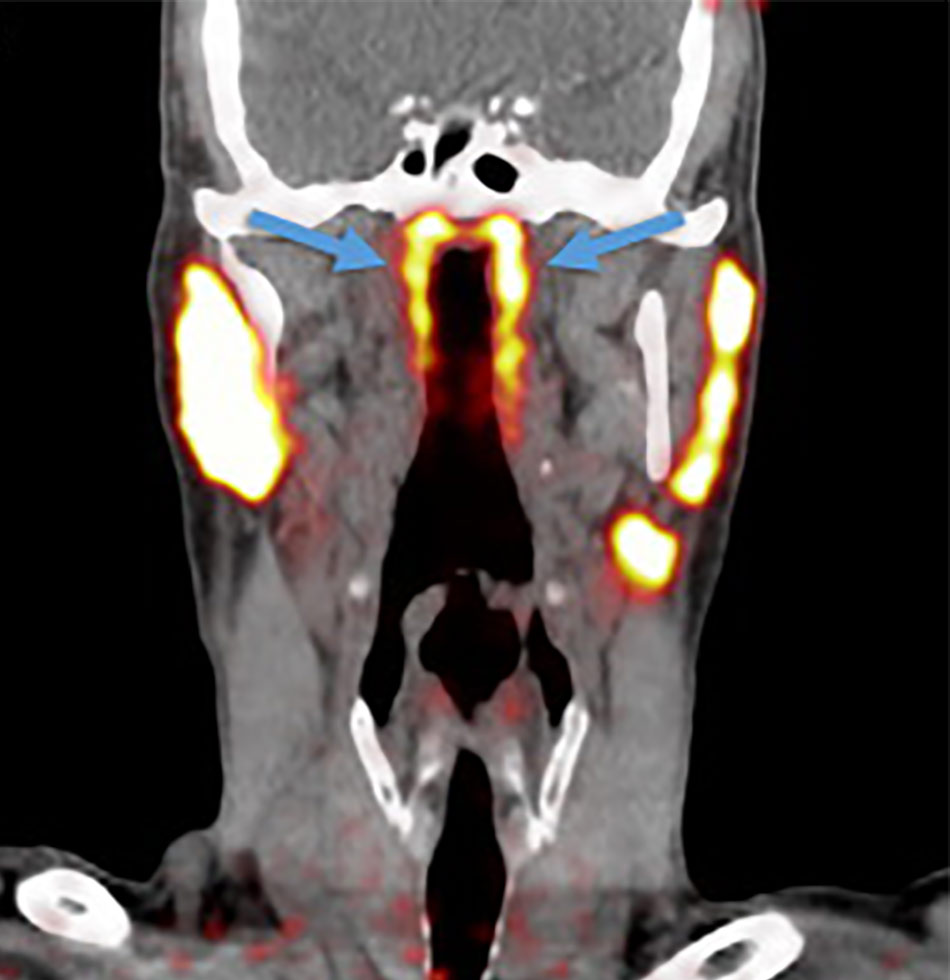

वैज्ञानिकों ने इंसानी शरीर में एक नए अंग का पता लगाया है. नीदरलैंड के वैज्ञानिक एक नए 'कैंसर स्कैन' की जांच कर रहे थे जब उन्हें गले में एक नए अंग का पता चला. रिसर्चर्स ने पाया कि इंसान के गले के ऊपरी हिस्से में ग्रन्थियों का एक ग्रुप है जिसके बारे में अब तक पता नहीं था.

वैज्ञानिकों ने शरीर में पता चले इस नए अंग को Tubarial salivary glands नाम दिया है. वैज्ञानिकों का मानना है कि यह अंग नाक के लूब्रिकेशन में मदद करता है.

नीदरलैंड के एम्सटर्डम के कैंसर इंस्टीट्यूट के वैज्ञानिक प्रोस्टेट कैंसर की जांच के लिए तैयार किए गए PSMA PET-CT नाम के स्कैन का परीक्षण कर रहे थे. इस दौरान डॉक्टर्स एक रेडियोएक्टिव ट्रेसर को मरीज के शरीर में इंजेक्ट करते हैं. रेडियोएक्टिव ट्रेसर की वजह से ही नए अंग का पता चला.

वैज्ञानिकों का कहना है कि ग्रन्थियों के जिस समूह का पता चला है कि वह 1.5 इंच लंबा हैं. यह salivary glands की तरह ही है. स्टडी के दौरान जिन 100 मरीजों की जांच की गई, सभी में यह अंग मौजूद था.